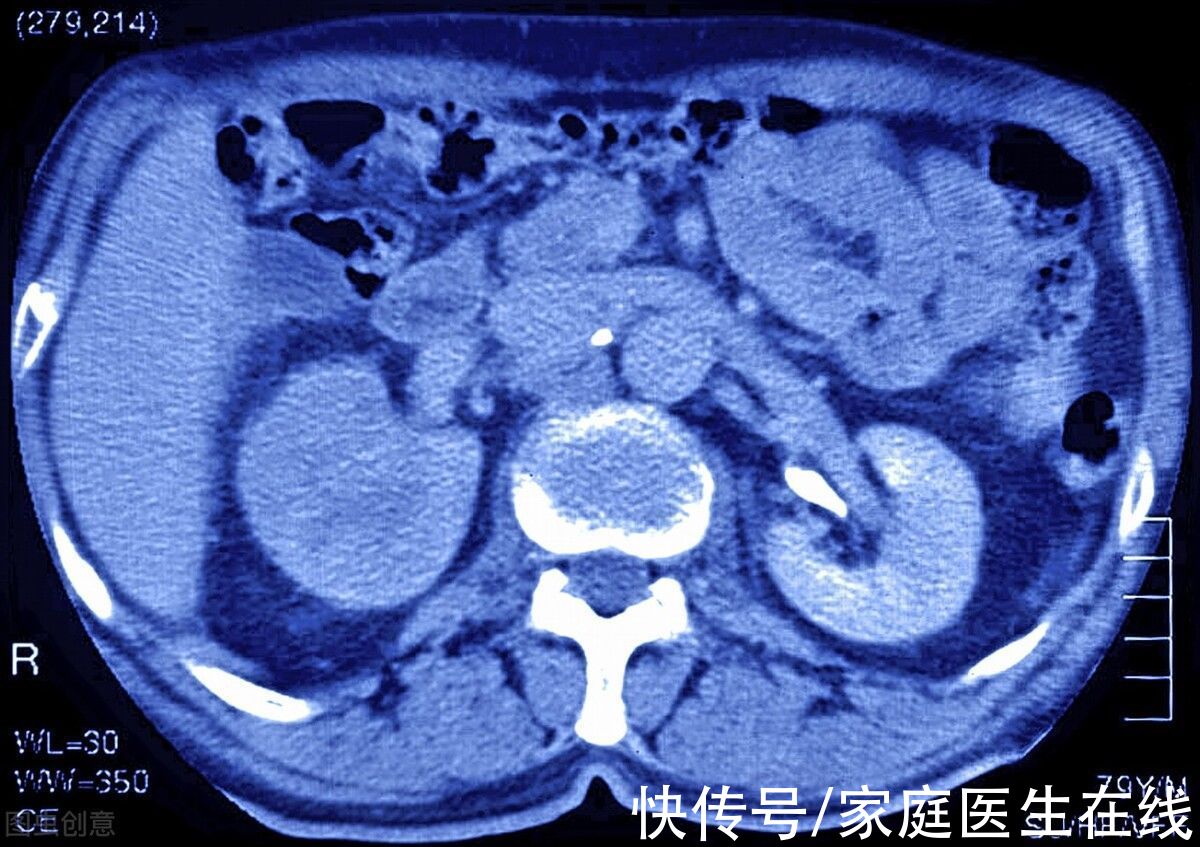

3、 诊断肾癌的方法

目前大多数医生会通过影像学检查来诊断肾癌,不过之后需要做进一步的病理学检查来确定病情。最常用的检查项目是B超,既不会产生辐射,也不会对身体造成伤害,通过B超能够发现直径1~2厘米的肿瘤,如果有异常情况,医生还会建议患者做核磁共振和CT以及X线片。